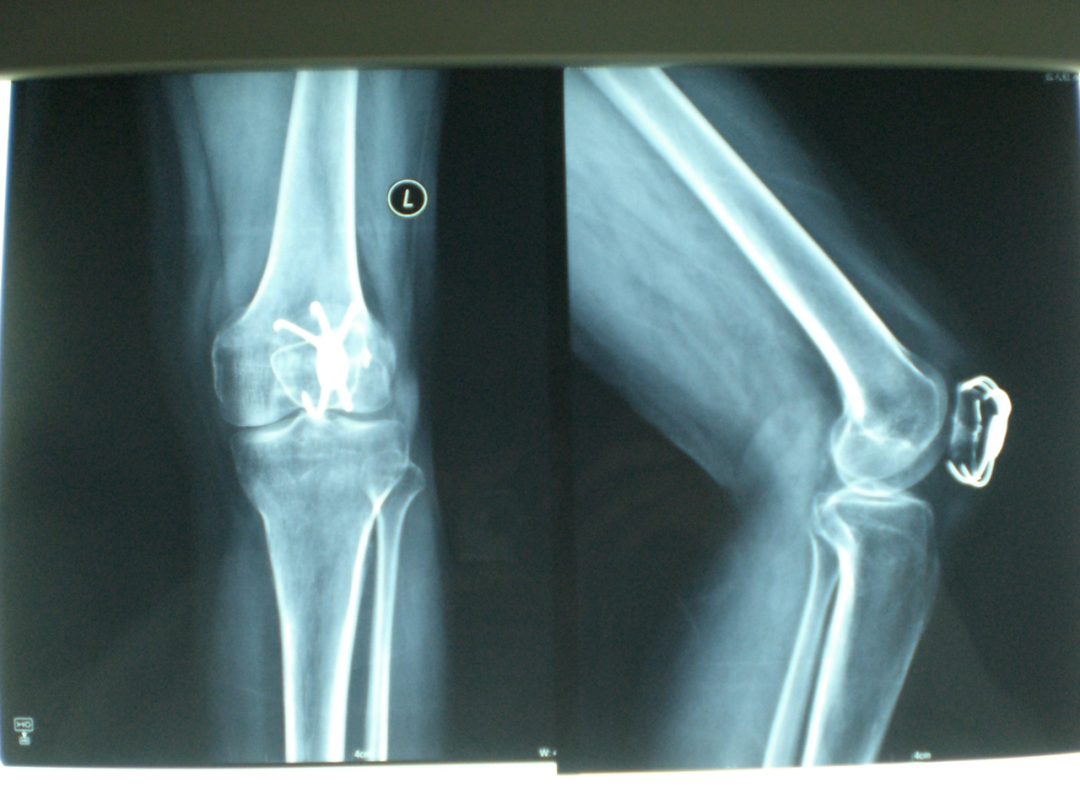

患者宋某,女,48岁,在2023年7月因跌倒致髌骨骨折,在骨科行髌骨骨折内固定术后出院,2024年10月返回我院取出髌骨内固定。在骨折治疗中,内固定是一种常见且重要的手术方法,它通过金属装置将骨折断端固定在一起,以促进骨折的愈合和恢复。然而,随着骨折的愈合和康复,患者常常会面临一个问题:内固定装置是否需要取出?下面,我们就让骨科医生告诉您。